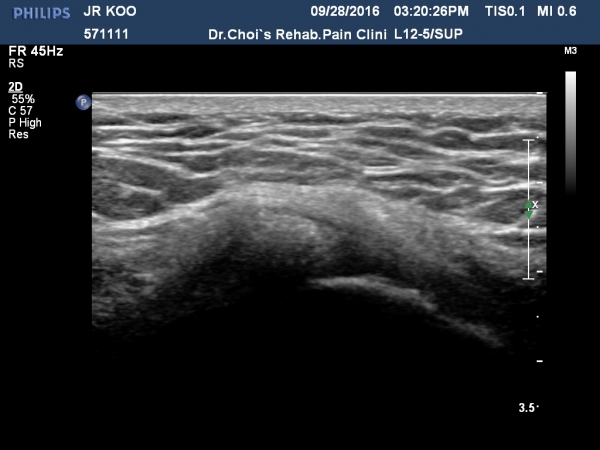

´ëÀüÀÚ È¾´Ü¸é°Ë»ç¿¡¼­ ¼ÒµÐ±Ù¿¡ ¼®È¸È­À½¿µÀÌ °üÂûµÊ(»çÁø 1, 2).